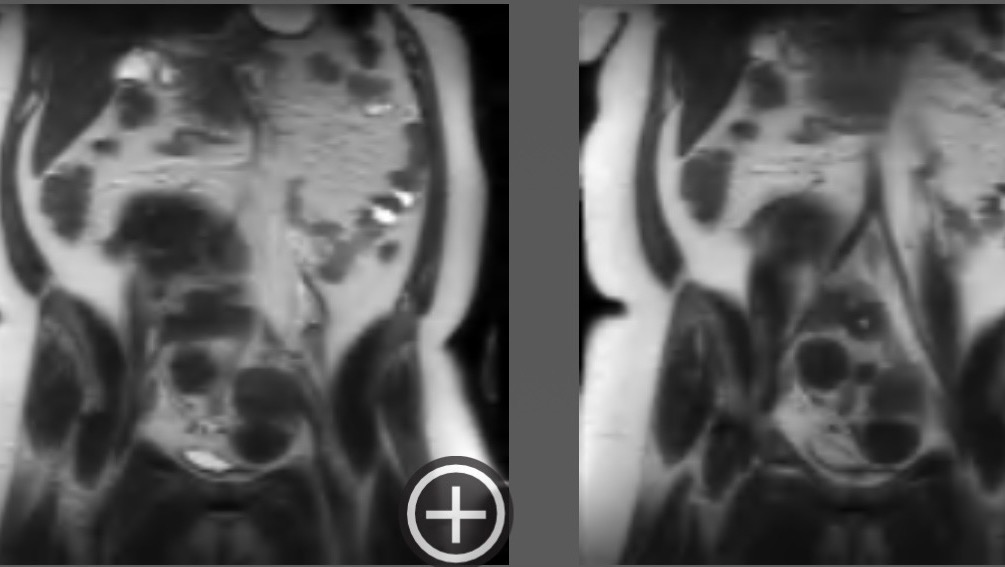

Uterine Fibroids are noncancerous growths of the uterus that are extremely common for Black women. Unfortunately, my pelvic sonogram showed a markedly enlarged uterus with 5 medium-sized fibroids and other smaller fibroids. (doctor informed me there’s 30+.) To give you an example of the sizes of my fibroids, they all vary between as small as a strawberry and as large as a grapefruit or small watermelon.

My doctors communicated that these fibroids have been living in me for roughly 9-10 years, and that one of my fibroids is the size of a 7-month-old child. So for that long, doctors throughout the years continued to ignore my symptoms and family history to the point where I managed to normalize and cope with the pain and symptoms I’ve felt. Knowing I’m about to feel like an entirely different person once they’re all removed has been very overwhelming. Please be patient with me. Thank you for reading and sharing. I genuinely appreciate all of your support, xo.